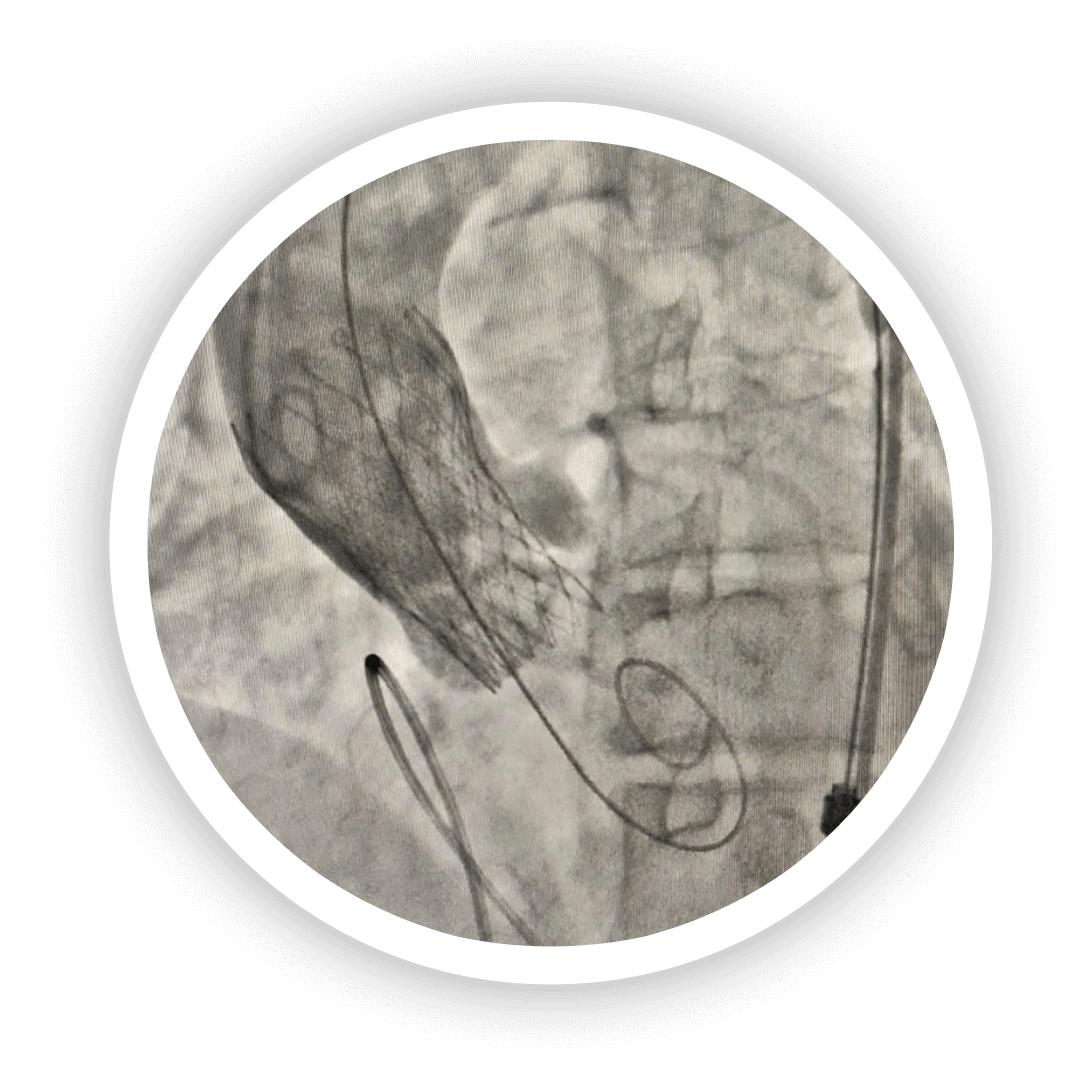

The Valve Clinic is the leading center for TAVI in Mumbai, offering world-class care for patients with severe aortic stenosis. As one of the best TAVI hospitals in Mumbai, we specialize in minimally invasive transcatheter aortic valve implantation, ensuring faster recovery and improved outcomes. Our expert team, advanced technology, and patient-centric approach make us the preferred choice for heart valve treatments. Trust us for safe, effective, and innovative cardiac care.

The Valve Clinic Gallery